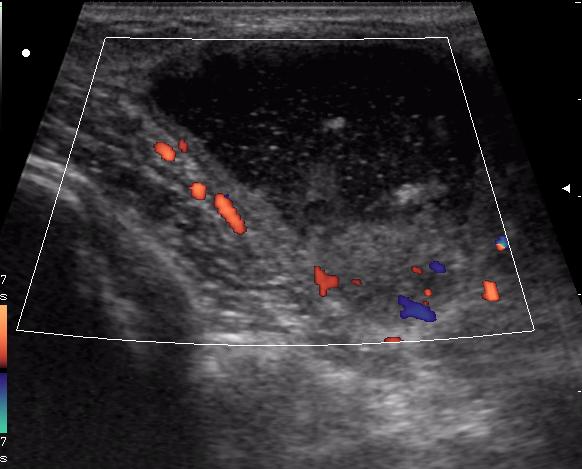

В клинику обратилась мать 11-летней девочки с жалобами на появление припухлости в подключичной области справа. Впервые заметили в феврале. За 4 месяца не интенсивный рост образования, с переходом на переднюю поверхность плеча, где кожа над ним на ограниченном участке (1.5-2см) имеет багрово-синюшную окраску.

Из анамнеза - ДТП осенью прошлого года.

(с д-зом Гематома(?) направлена на УЗИ)

достоверной связи с мышцами не увидела. Но на задней проекции включения определяется солидное образование. это может быть лимфоузел?

холодный абсцесс